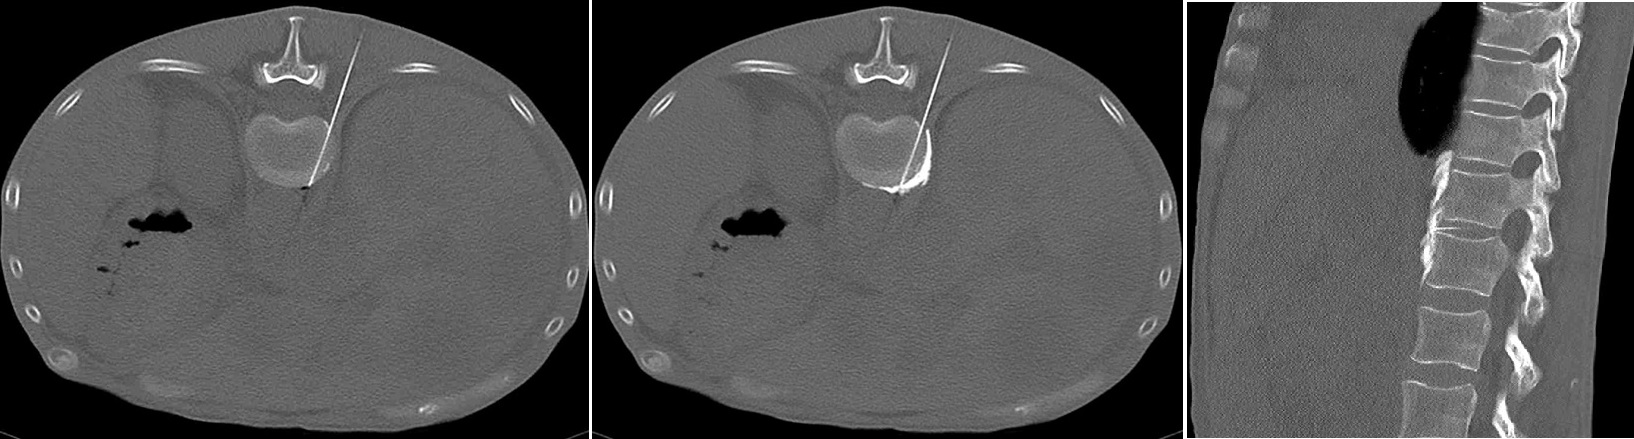

原発性肺癌、肺転移に関しては、近年RFA治療が承認されたため、呼吸器外科と連携し、肺RFAが可能です。転移の場所が深く、切除すると広範囲の肺切除を必要とするような症例が良い適応です。また、切除+RFAという選択枝もベストマッチです。是非、ご紹介ください。

肺RFA